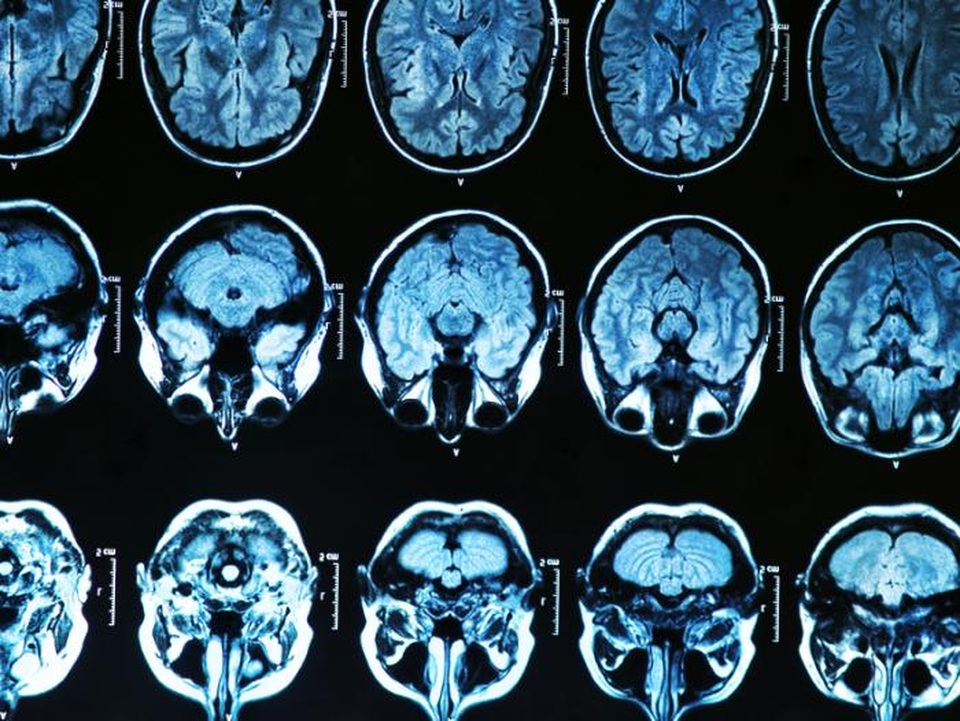

Các nhà khoa học vẫn đang cố gắng để hiểu được những phức tạp, những thay đổi diễn ra trong bộ não của những người bị bệnh Alzheimer. Tuy nhiên, những triệu chứng xuất hiện đầu tiên là lớp lắng đọng bất thường của amyloid beta và protein tau được hình thành trong não dần dần làm tắc nghẽn các tế bào não để não ngừng hoạt động và chết. Cần phải tìm cách để xác định và ngăn chặn những thay đổi não sớm trước khi chúng gây hại cho não.

Vì vậy, nhóm nghiên cứu đã sử dụng "chuột htau" những con chuột biến đổi gen có các hình thức của con người về loại protein tau bị lỗi trong bệnh Alzheimer và phá vỡ cấu trúc tế bào nội bộ quan trọng được gọi là các vi ống. Họ đo mật độ loãng xương ở chuột htau trước khi chúng phát triển dấu hiệu quan trọng của chuột tau bất thường. Kết quả cho thấy, giảm đáng kể mật độ loãng xương so với những con chuột bình thường, đặc biệt là ở chuột đực. Những con chuột htau được kiểm tra kỹ hơn đã có những thay đổi tế bào chính trong một vùng não được gọi là “vùng não bộ làm phát sinh cảm giác cô đơn (DRN)” là cấu trúc quan trọng của bộ xương người lớn. Các DRN cũng sản xuất nhất của serotonin trong não.

Các nhà nghiên cứu cũng cho thấy mức độ cao hơn của protein tau bất thường trong cùng khu vực của não sớm nhất là 4 tháng tuổi ở chuột htau. Họ đưa ra kết luận rằng, phát hiện của họ cho thấy giảm mật độ loãng xương xảy ra sớm hơn so với thoái hóa não trong mô hình thử nghiệm trên chuột mắc bệnh Alzheimer và những biến đổi trong protein tau xảy ra ở các tế bào serotonin – sản xuất ở phần cuống não của những con chuột. Cần nghiên cứu sâu hơn nữa để có thể thấy rõ ràng cơ chế phân tử liên kết loãng xương làm giảm serotonin ở bệnh Alzheimer.